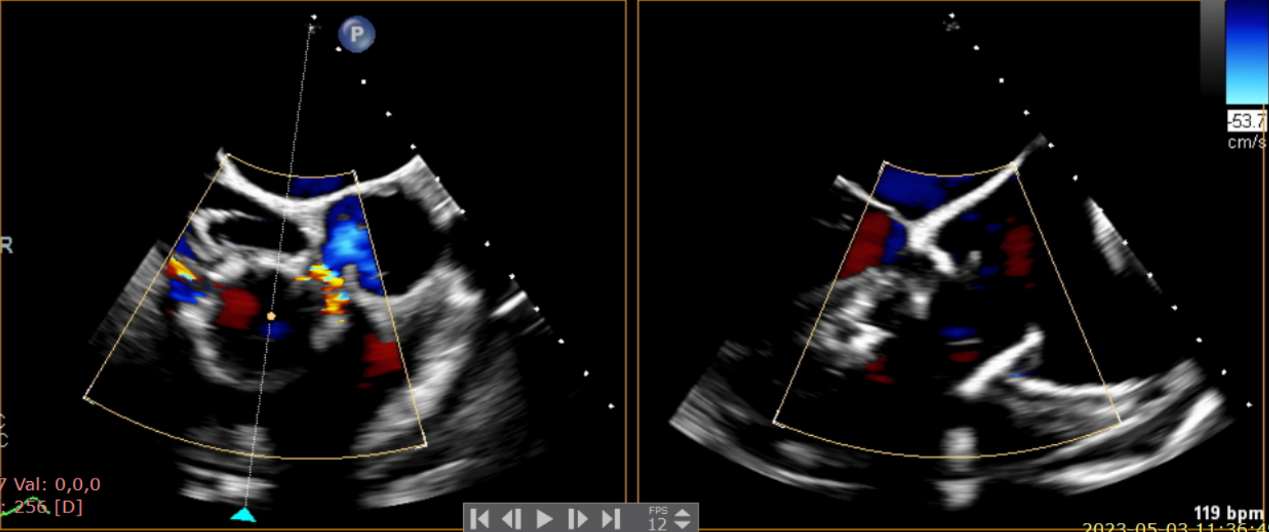

近日,美國紐約Montefiore醫(yī)學中心(Montrefiore Medical Center)的Azeem Latib教授團隊成功應用LuX-Valve Plus經(jīng)血管三尖瓣置換系統(tǒng)為兩位三尖瓣大量反流的患者完成三尖瓣置換手術。術后超聲顯示人工三尖瓣植入穩(wěn)定,瓣葉啟閉良好,僅殘余微量瓣周漏?;颊哂谑中g室即刻拔除氣管插管,血流動力學改善顯著。此次手術是LuX-Valve Plus于紐約的首次臨床應用,治療效果優(yōu)異。

術前超聲提示大量三尖瓣反流

術中輸送器在超聲引導下調整位置

術后超聲提示無瓣周漏